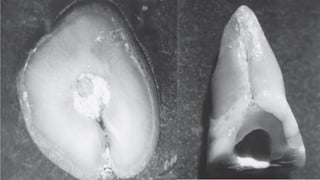

Although root shape in cross section is variable, there are seven general

configurations: round, oval, long oval, bowling pin, kidney bean, ribbon, and

hourglass.

Shape and location of canals are governed by root shape (in cross section).

Different shapes may appear at any level in a single root. For example, a

root may be hourglass shaped in cross section at the cervical third, taper to

a deep oval in the middle third, and blend to oval in the apical third; the

number and shape of canals in each level will vary accordingly." Importantly

though, a canal is seldom round at any level.

To assume that it is may result in improper canal preparation

a canal occupies the center of the

root. When there are two canals

in a root, each will often occupy

the center of its own root “bulge.”